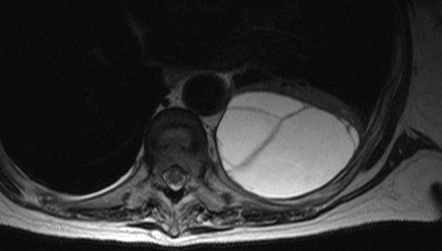

MRI scan of septated empyema

From the collection of Najib Rahman, RTU, Oxford